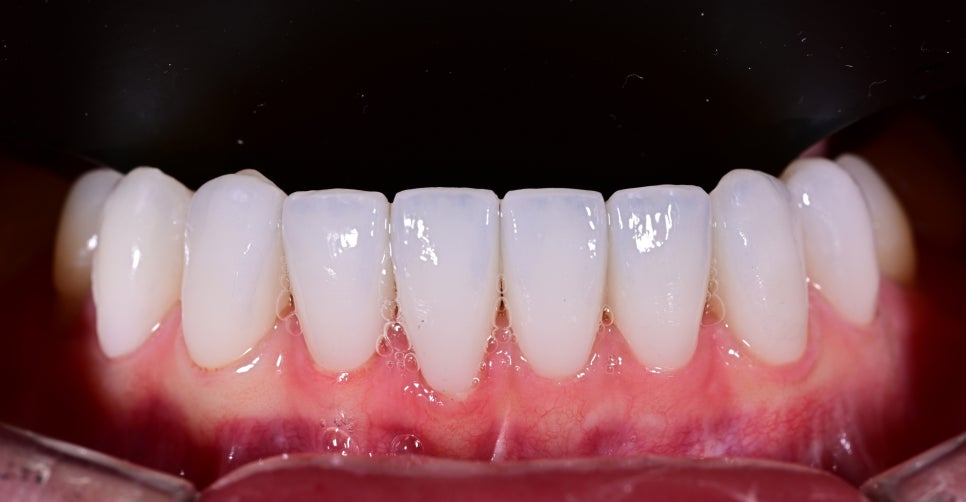

- 기존 임플란트 보철의 어색한 부분 개선

앞니 임플란트는 자연치와 달리 빛 투과감이나 잇몸과의 연결감에서 차이가 나기 쉬워 보철 디자인이 매우 중요합니다.

기존 보철의 색감과 형태, 조화도를 다시 점검하여 주변 치아와 보다 자연스럽게 이어지도록 보철을 재설계했습니다.

기존에는 임플란트 부위가 주변 치아와 미묘하게 다르게 보여 앞니 전체의 통일감을 해치고 있었지만, 치료 후에는 앞니의 색감과 형태, 비율이 훨씬 부드럽게 연결되면서 전체 인상이 한층 정돈되고 자연스러워졌습니다.

또한 너무 차갑거나 인위적인 흰색이 아니라 환자분 이미지에 어울리는 깨끗하고 고급스러운 화이트 톤으로 완성되어 웃을 때의 분위기 자체가 훨씬 밝아졌습니다.